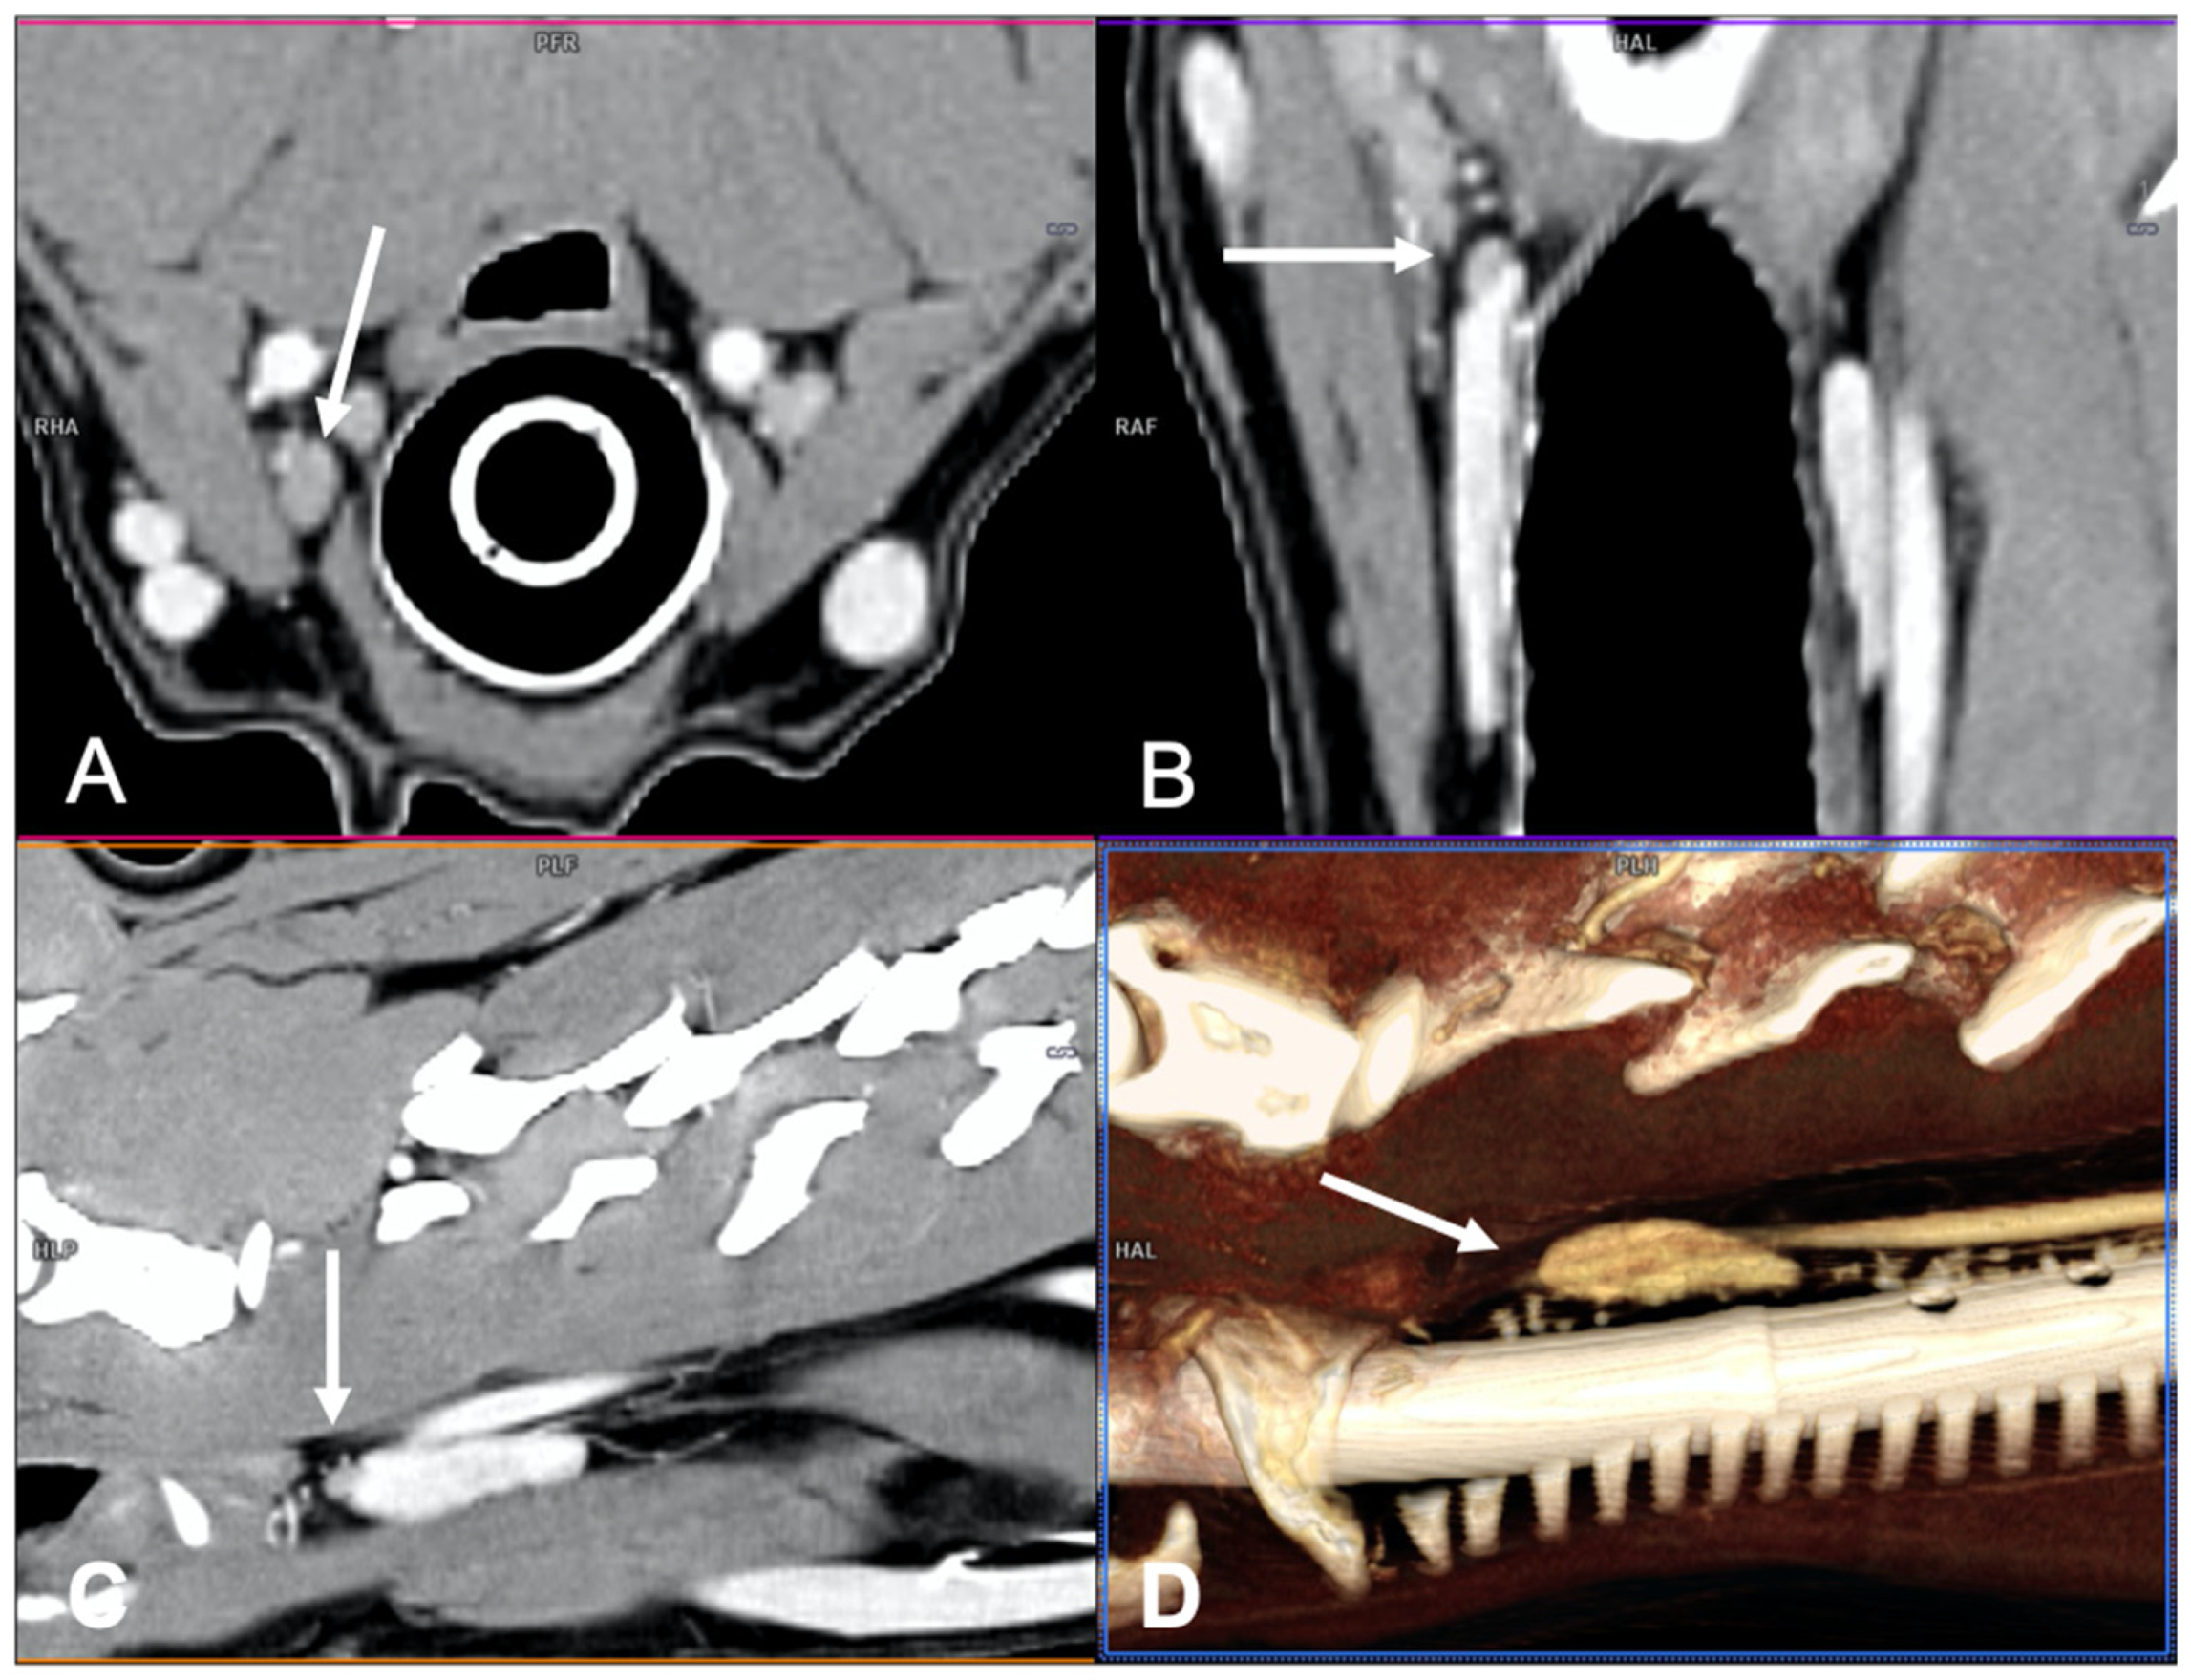

Only two dogs with parathyroid gland hyperplasia (Figure 6) were included in the study; the shape (one rounded and one ovoid) and the contrast enhancement (one homogeneous and one heterogeneous) were variable.

Figure 6.

CT appearance of parathyroid gland hyperplasia. Post-contrast dorsal (A) and right parasagittal (B) CT reconstruction of one dog with parathyroid gland hyperplasia (arrow) at the level of the right internal parathyroid. The parathyroid is ovoid-shaped and homogeneously contrast-enhancing. Note the marked difference in attenuation between the parathyroid (hypoattenuating) and the adjacent thyroid tissue.